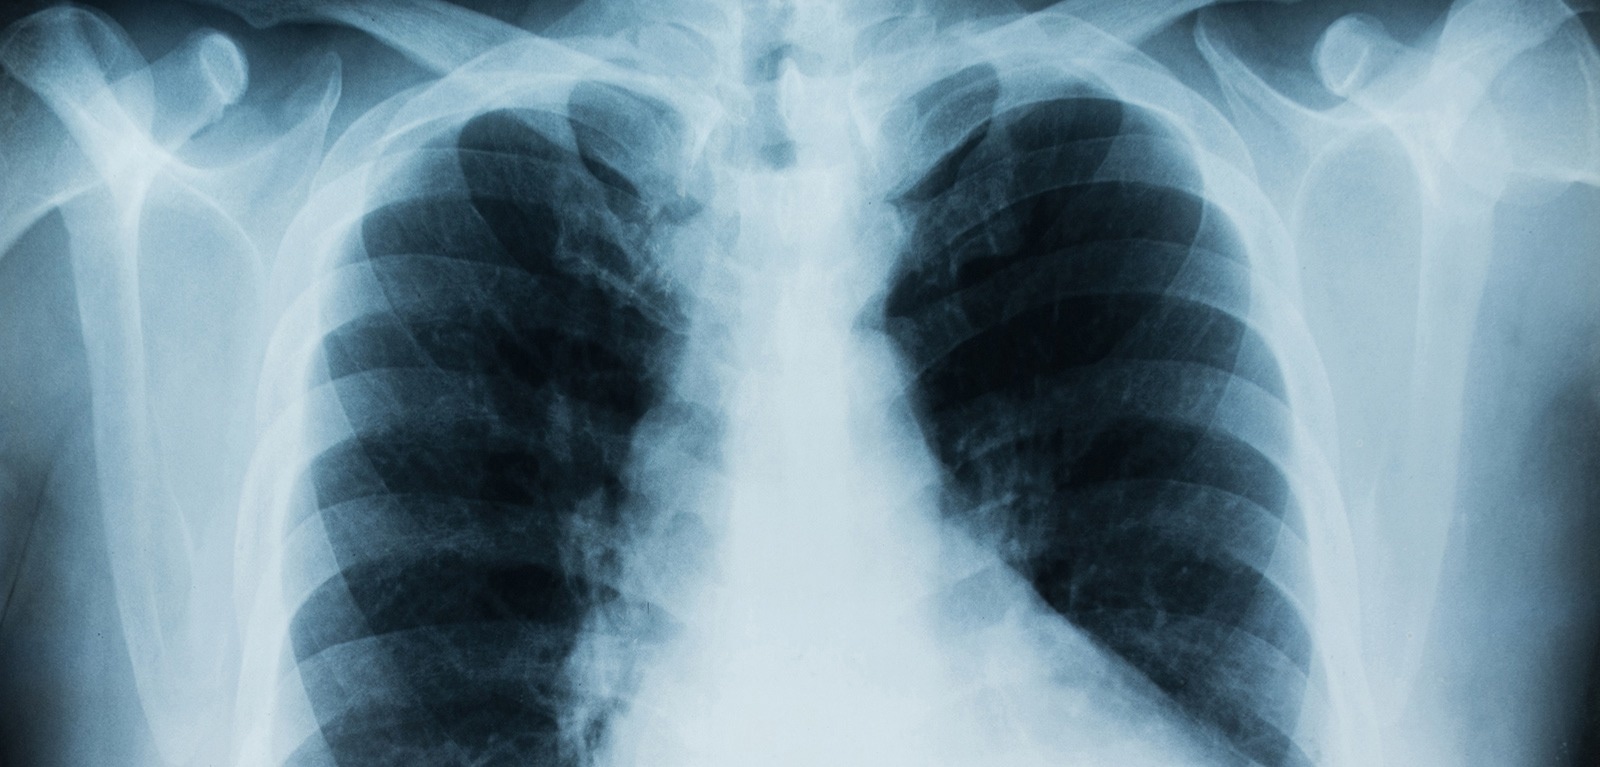

Image Credit: Queen’s University Belfast

To conduct their study the researchers looked at the bacterium Achromobacter which can cause chronic lung infection and tissue damage in the airways.

The researchers observed that Achromobacter infection leads to damage in lung structure and causes severe illness if the specialized secretory pathway is functional, but not if bacteria carry mutations in the secretion system.